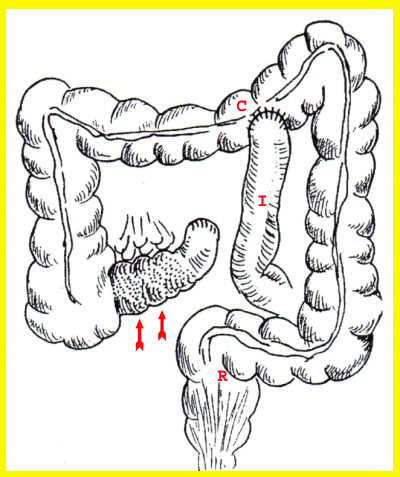

- Ileotransversostomy - שבו יוצרים קשר חדש בין לולאת מעי דק תיכונה (פרוקסימלית) לנגע לבין הכרכשת הרוחבית. ניתוחים אלה מבצעים בעיקר כאשר לחולה יש חסימה שלמה של המעי הדק ומצבו הכללי או הממצאים בבטן אינם מאפשרים ניתוח נרחב יותר. הפסקת מעבר המזון דרך הקטע הנגוע מאפשרת ריפוי המעי והקלה בתסמינים (איור 4.1).

- Bypass by Exclusion - בניתוח זה מנתקים את קטע המעי הנגוע מהקטע הבריא. את הקטע הבריא מחברים לכרכשת הרוחבית. הקטע הנגוע נסגר בקצהו התיכון (הפרוקסימלי), והוא מתנקז למעי העיוור (צקום) (איור 4.2). הפרדה מושלמת זו בין שני חלקי המעי מונעת מעבר של מזון דרך הקטע הנגוע, ובמשך השנים הוא מידלדל. יש דיווחים בספרות על שכיחות גבוהה יותר של שאתות ממאירות בקטע זה של המעי. ניתוחי מעקף מבוצעים רק בחולים מבוגרים בעלי סיכון גבוה לניתוח או בחולים שבוצעו בהם ניתוחים חוזרים ומעוניינים לשמר בהם חלקים גדולים ככל האפשר מהמעי הדק. ניתוחים אלה מבוצעים גם בחולים בעלי מורסות המצריכות בידוד של קטע המעי הנגוע בלי לכורתו.